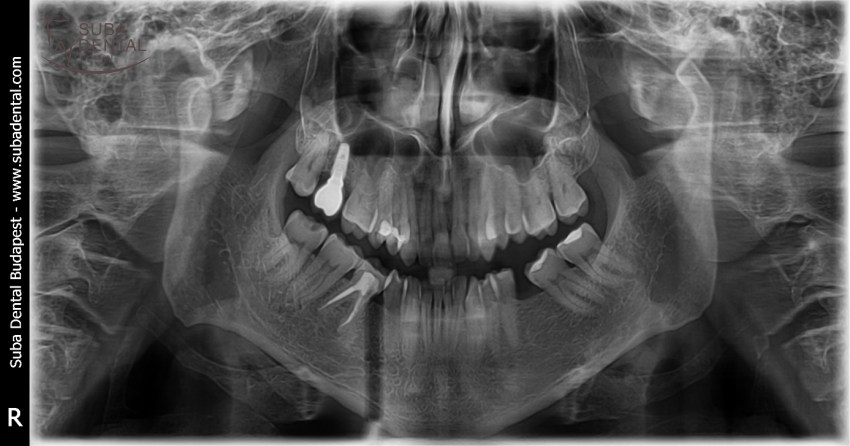

Panoramic radiograph of the initial condition. Several teeth were beyond repair, with all upper teeth due for removal

After 3 months of healing the CT scan revealed that bone height was inadequate on both sides, and a sinus lift was necessary, which could not be performed in the same sitting with implant surgery due to inadequate bone height. In the second sitting bone graft was performed in the upper arch and the lower implants were installed (2 per quadrant).